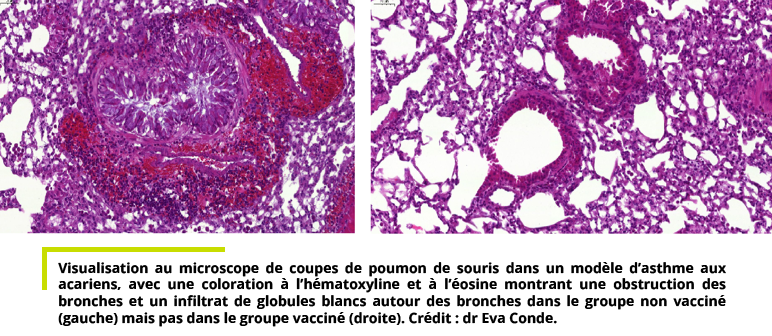

Cette exposition aux acariens et autres allergènes déclenche une surproduction d’anticorps appelés immunoglobulines E (IgE) et de protéines appelées « cytokines de type 2 » (en particulier les interleukines IL-4 et IL-13) dans les voies aériennes. Ce phénomène entraine une cascade de réactions aboutissant à une hyperréactivité des voies respiratoires, une surproduction de mucus et une éosinophilie (un taux trop élevé de globules blancs appelés éosinophiles dans les voies aériennes).